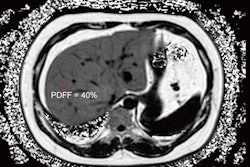

Velocity streamlines of the portal vein measured using 4D flow MRI in a cirrhosis patient (a 62-year-old male), shown at the cardiac cycle time t = 84 ms. A cut-plane (white marker) matching the 2D flow image plane was used to quantify the 4D flow parameters in the main portal vein.Shan Cai and ISMRM